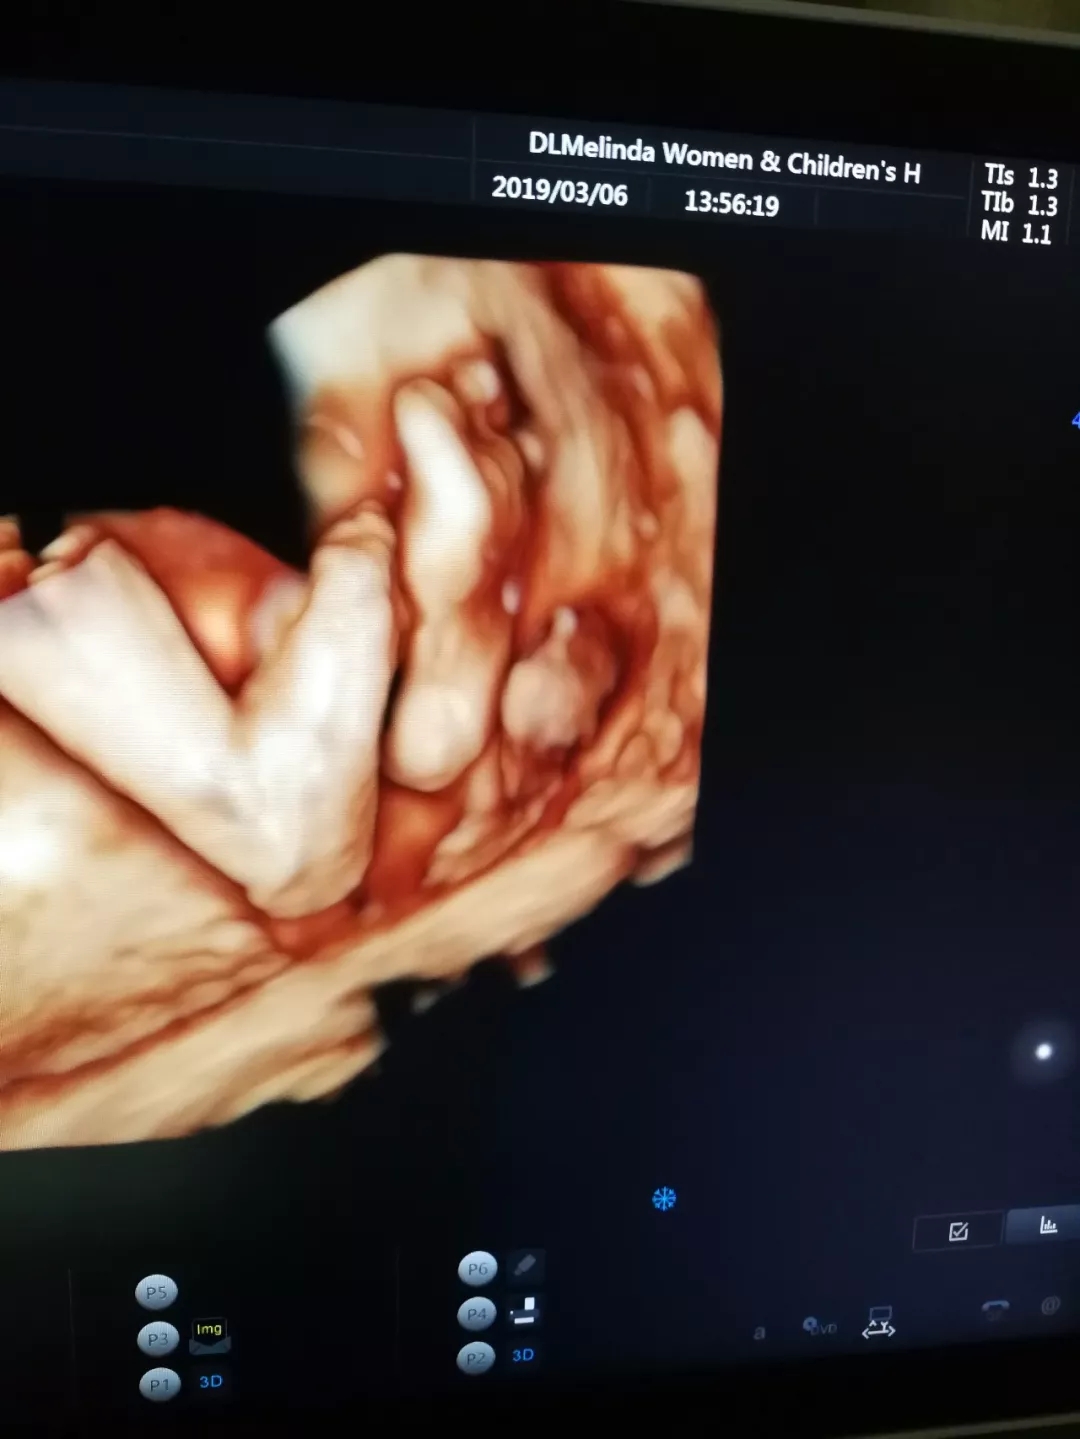

与胎宝紧密相连280天里,一次次胎动是你们之间独特的交流方式,而这时,我们更加好奇胎宝每天都在妈妈肚子里干什么呢?看看这些四维彩超抓拍的胎宝的小模样吧!以下为胎宝的自白时间哦~!

但通过美琳达的四维彩超画面中

TA们的活泼好动,萌萌的表情

已经说明了一切